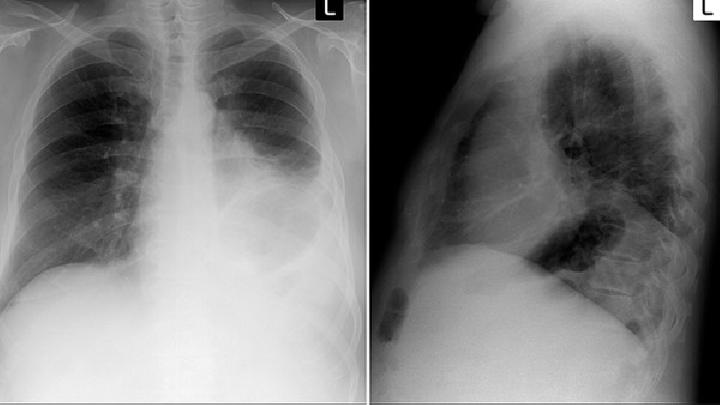

小细胞肺癌又称小细胞未分化癌,是肺癌中恶性程度最高的一种,约占原发性肺癌的1/5。患有该病的患者一般比较年轻,多在40-50岁左右,并且多有吸烟史,男性患者的比率高于女性患者。癌细胞常侵犯管外肺实质,易与肺门、纵隔淋巴结融合成团块。癌细胞生长快,侵袭力强,远处转移早,常转移至脑、肝、骨、肾上腺等脏器。这种类型的肺癌对放疗和化疗比较敏感。

1、咳嗽:咳嗽是比较常见的现象,大多数为刺激性干咳,可出现持续性、高调金属音咳嗽。咳嗽多伴少量黏液痰,当继发感染时可合并脓痰

2、咯血:多为痰中带血或间断血痰,少数因侵蚀大血管出现大咯血。

3、胸闷、气短:肿瘤引起支气管狭窄,或肿瘤转移至肺门或纵隔淋巴结,肿大的淋巴结压迫主支气管或气管隆突。

4、胸痛:肿瘤侵犯胸膜、肋骨或胸壁,引起不同程度的胸痛肿瘤压迫肋间神经,胸痛可累及其分布区。